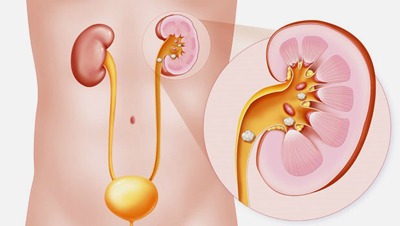

سنگ کلیه زمانی ایجاد می شود که مواد معدنی مانند کلسیم، اگزالات و فسفات در مجاری کلیه متمرکز و به کریستال تبدیل می شوند. اگر می خواهید از تشکیل این سنگ ها پیشگیری کنید، باید از علل ابتلا به این سنگ ها آگاه باشید. 10 علت شگفت انگیز که خطر ابتلا به سنگ کلیه ژنتیک: در برخی از افراد، بدن …